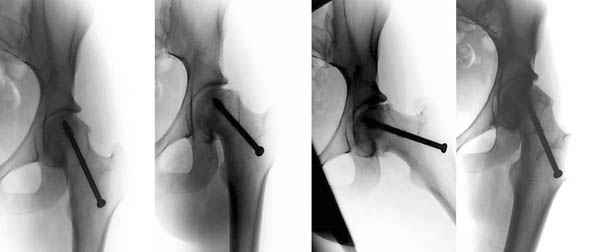

Если стабильность юношеского эпифизиолиза доказана, тогда можно провести коррегирующие операции. Все открытые методы репозиции опасны высоким процентом осложнений из-за повреждения кровоснабжения головки.

Еще Trueta and Harrison, JBJS, 35-B:442, 1953; потом Sevitt and Thompson, JBJS, 47-B:560, 1965 доказали, что медиальная циркумфлекс артерия доставляет от 66-80% крови в головку бедра, поэтому важным является профилактика повреждения медиальной артерии.

Здесь представлен один из случаев остеотомии на шейке после остаточного явления юношеского эпифизиолиза из Flip Trochanteric доступа.